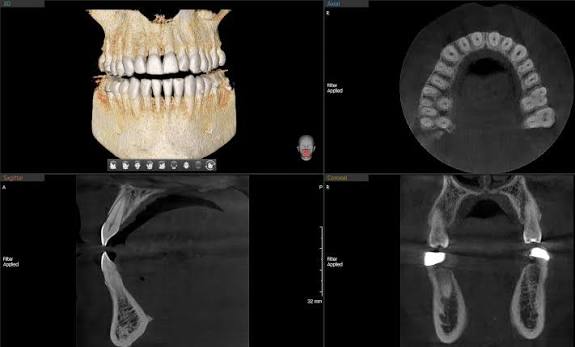

· Posedujemo rentgen kabinet za snimanje zuba (3D digitalni ortopan, Telerendgen, intraoralni rentgen sa senzorom) najnovije generacije, sa redukovanom (smanjenom) dozom zračenja!

Razlika između običnog i 3D Ortopan snimka?

3D je savremenija i bolja verzija koja stomatologu omogućava da vidi sve dimenzije mnogo bolje i postao je zlatni standard pre ugradnje implantata jer omogućava sa se vide širina kosti, visina i gustina kao i odnos prema okolnim anatomskim strukuturama kao što je npr mandibularni kanal, pod sinusa, itd, a to su sve podaci koji su neophodni za uspešnu ugradnju implantata.